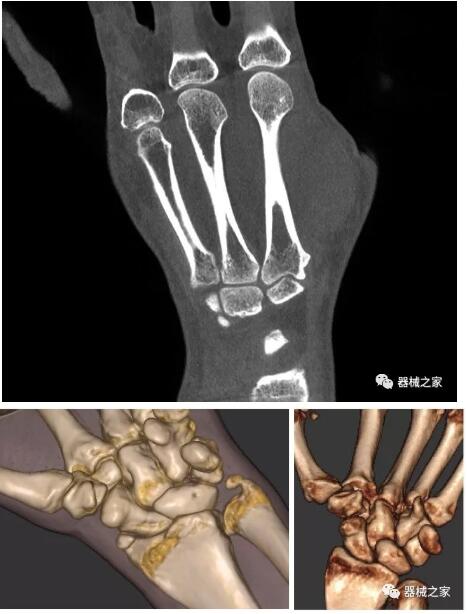

以上介紹的CT均來自國外同一家公司,這些CT均配置了可視化軟件,可以進(jìn)行切片、3D重建以及大型CT附帶的所有典型的操作功能。

以下是這些“特立獨(dú)行”的CT所拍出來的圖像: